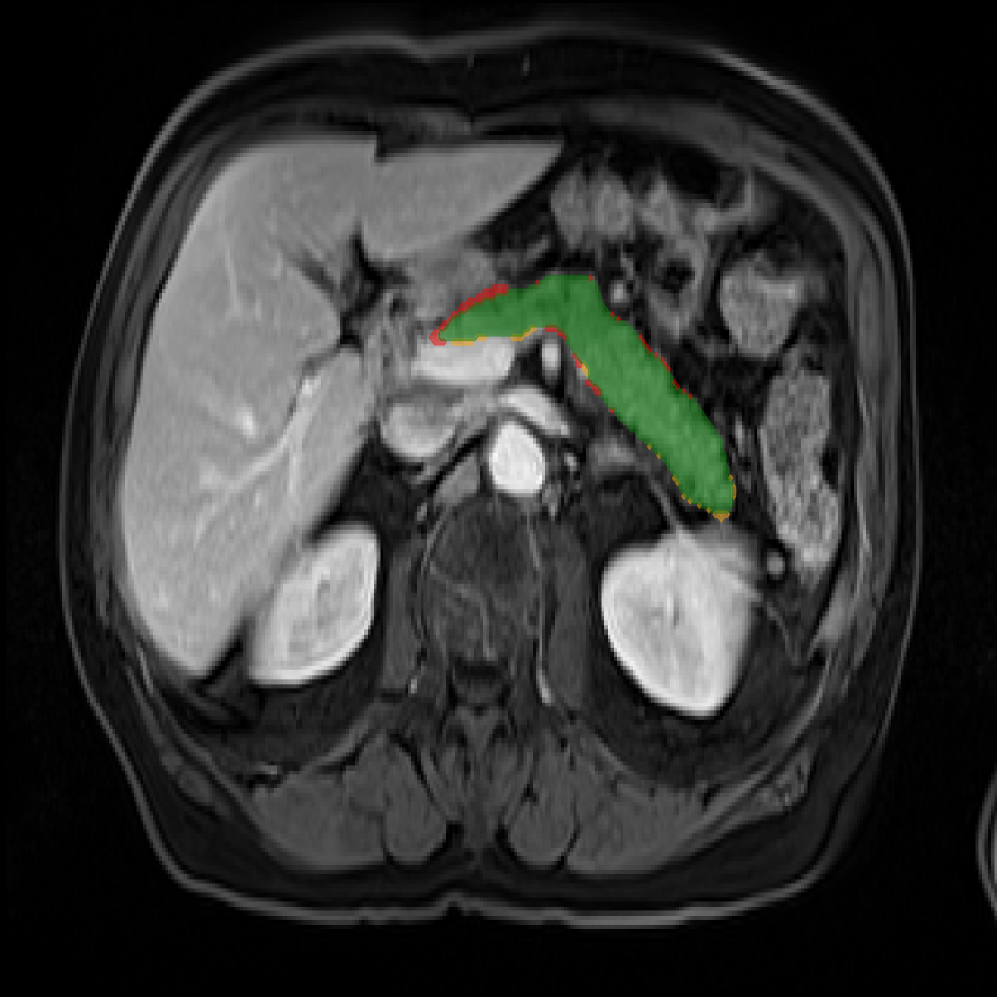

Accurate pancreas segmentation is a critical prerequisite for precise cyst analysis and classification. Recently, we developed PanSegNet [zhang2025large], a novel segmentation architecture incorporating linear self-attention layers [zhang2022dynamic] within the nnUNet framework [isensee2021nnu] to enhance global information modeling capabilities while maintaining computational efficiency (Fig. 1). PanSegNet demonstrated exceptional segmentation performance across both T1W and T2W modalities, achieving mean dice scores of 86.817.30% and 89.626.38%, respectively (Table 1, Fig. 2b-c). This performance significantly exceeded that of Swin-UNETR [hatamizadeh2021swin], one of the most used state-of-the-art transformer-based medical segmentation models, which achieved dice scores of 79.091.40% and 76.290.66% for T1W and T2W, respectively (). In this study, we integrated PanSegNet into our Cyst-X engine along with a classifier for risk prediction. In Section 2.2, we show that the choice of segmentation model affects the classification results. The performance advantage of PanSegNet was consistent across all seven medical centers, demonstrating robust generalization despite variations in imaging protocols and equipment (Table 1). This cross-institutional reliability is particularly important for clinical applications, where model performance must remain consistent regardless of imaging site or acquisition parameters.

2.2.1 Importance of accurate pancreas segmentation in classification

To assess the importance of accurate pancreas segmentation in classification, we evaluated how different ROI sources affect DenseNet-121’s performance. Specifically, we compared classification results using ROIs generated by PanSegNet and Swin-UNETR, both under centralized learning, against a baseline using radiologist-defined ROIs. As shown in Table 2, using PanSegNet’s masks resulted in only a modest performance decline, reflecting its strong segmentation quality. In contrast, Swin-UNETR led to a more substantial drop, demonstrating that inferior segmentation can directly compromise classification. For 3-class classification, the mean AUC dropped from 75.59% (radiologist ROI) to 72.26% with PanSegNet, and further to 66.95% with Swin-UNETR on T1-weighted images. On T2-weighted scans, the AUC declined from 81.09% to 74.18% (PanSegNet) and to 69.63% (Swin-UNETR). A similar trend was observed in 2-class classification: on T1W, AUC dropped from 78.13% to 74.84% (PanSegNet) and 70.20% (Swin-UNETR); on T2W, from 82.37% to 77.01% and 68.92%, respectively. These results emphasize that accurate segmentation—particularly via PanSegNet—is not only essential for volume estimation but also critical to preserving downstream classification performance in the Cyst-X pipeline.